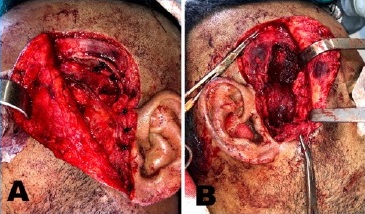

Low condylectomy was performed bilaterally using a Lindemann bur. A chisel and hammer were used to disconnect the condyle from the glenoid cavity. Then, reanatomization of the joint surface was performed with a multi-laminated bur. After condylar arthroplasty, muscular interposition of the pedunculated flap of the temporal muscle was conducted, filling the joint cavity, using Vicryl 3.0 for its fixation and covering the TMJ region, thus reducing the chances of recurrence (Figure 4).

During the execution of the technique, hemostasis was induced with electrocautery and ligation of the superficial temporal arteries. Abundant irrigation was applied with 0.9% saline solution. Layer-by-layer synthesis with Vicryl 4.0 was performed in the musculature, and 3.0 nylon was used for skin closure in the Al-Kayat incision. Compressive dressing was employed with gauze, micropore, and bandage and maintained for 48 hours.